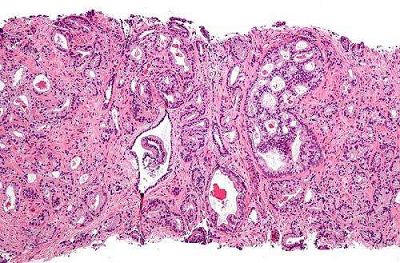

PSA筛查能够显著降低前列腺癌死亡的风险

最近两项重要的前列腺癌筛选临床试验提供证据表明,癌症筛查能够显著价格低前列腺癌死亡的风险。这一发现表明目前常规的胰腺癌检测手段需要做出修改。然而,目前还难以证明加重癌症筛查的比例的益处是否会大于过度诊断以及过度治疗所带来的风险的增高。

目前,美国疾病预防工作组(USPSTF)强烈反对使用前列腺癌特异抗原(PSA)作为检测癌症发作的风险,原因是由于这种方法对于降低前列腺癌患者的死亡风险帮助很低。相关数据分别来自ERSPC以及PLCO两项临床试验。其中,ERSPC显示出该检测方式具有降低患者死亡风险的效果,而PLCO则没有这一发现。结果的不确定性导至该检测手段受到了USPSTF的抵制。

(图片来源:Wikipedia)

为此,来自密歇根大学以及NIH的研究者们希望了解这两项临床研究的结果是否存在差异,以及接受PSA检查能否实际降低患者的死亡几率。通过建立数学模型,作者发现ERSPC与PLCO的试验结果其实并无差异,也就是说两项试验均表明PSA筛查能够显著降低胰腺癌的死亡风险。相关结果发表在《Annals of Internal Medicine》杂志上。

针对这一结果,来自几年凯瑟琳斯隆癌症中心的研究者们希望能够有利于停止有关PSA检测能否降低患者死亡率的纷争。研究者们应当将研究的重点放在这种筛查手段所带来的好处能否大过过度诊断与过度治疗所导至的负面效应。